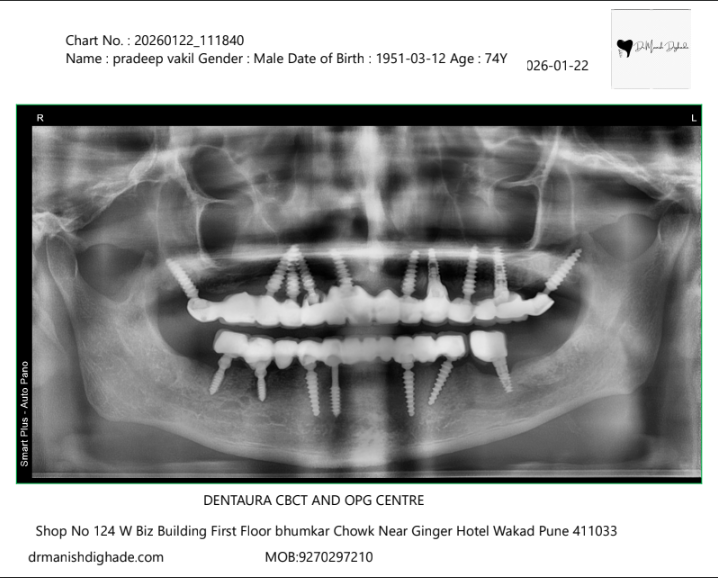

X-Ray Analysis

OPG โ After

Radiographic Findings

Clinical Observations: Multiple implants placed in both upper and lower jaw Full arch fixed prosthesis visible Implants are strategically angled (basal/tilted placement) Good distribution across the arch for load balance Strong bone anchorage achieved ๐ง Simple Explanation (Patient Language) We have placed artificial roots (implants) in the jaw bone These implants support fixed teeth (not removable) Because implants are spread across the jaw, chewing force is evenly distributed This allows the patient to eat normally again